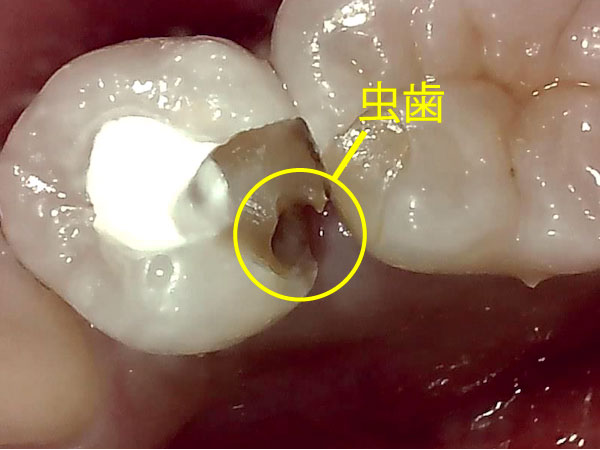

初診時の口腔内画像

古い詰め物(レジン)の一部を取り除いたところ、詰め物の下に虫歯が見えています。

前院では、この虫歯が原因で、歯の神経を取ったと思われます。本来であれば、この虫歯を完全に取り除いてから根管治療へ移行しなければなりませんが、虫歯が残ったまま治療を進めていたようです。